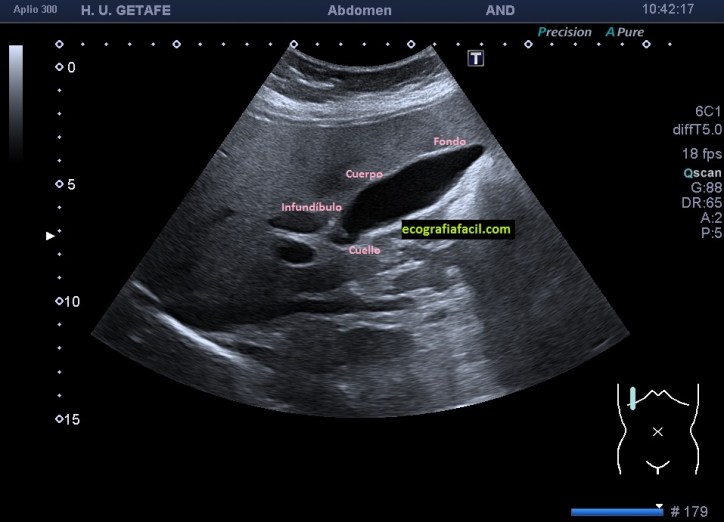

Lo primero, conocer la anatomía, no siempre se ve así de bonita…y el cuello es esencial buscarlo siempre, puede haber piedras impactadas ahí, en ocasiones de pequeño tamaño, lo que hace que tengamos que ser concienzudas.

En esta primera imagen observas la normalidad de la vesícula biliar, donde puedes ver una ecoarquitectura sacular, anecoica, de paredes finas, con una excelente capacidad de transmitir el sonido. Las ayunas hacen que la vesícula se vea repleccionada.